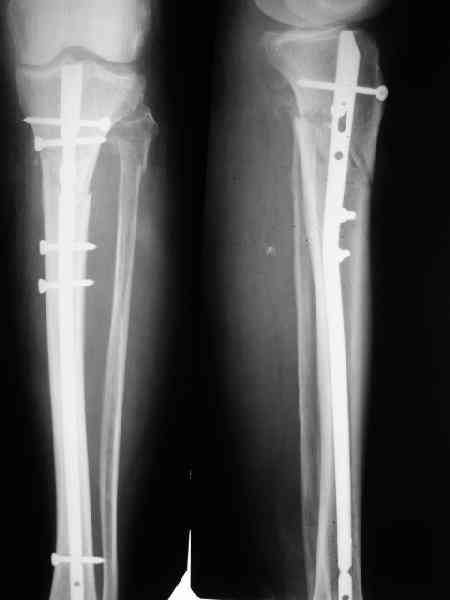

Пациенту М., 30-ти лет, 1,5 года назад в одной из московских больниц был выполнен остеосинтез бедренной кости штифтом UFN (диаметр штифта 9 мм).

К нам больной поступил с признаками ложного сустава бедренной кости, перелома

штифта и дистального блокирующего винта (images 1,2,3).

27 марта выполнено удаление блокирующих винтов (сломанный винт пришлось высверливать цапфен-бором), сломанного штифта (дистальный фрагмент удален через канал, образованный разверткой из коленного сустава - image 4),

рассверливание костно-мозгового канала, реостеосинтез штифтом UFN (при проведении штифта в дистальном отломке мы использовали поляризующий винт, диаметр штифта 10 мм). После операции в связи гемартрозом дважды (на 1 и 3 сутки) выполняли пункцию коленного сустава. Сейчас признаков скопления жидкости в полости сустава нет. Послеоперационные рентгенограммы - images 5, 6, 7.